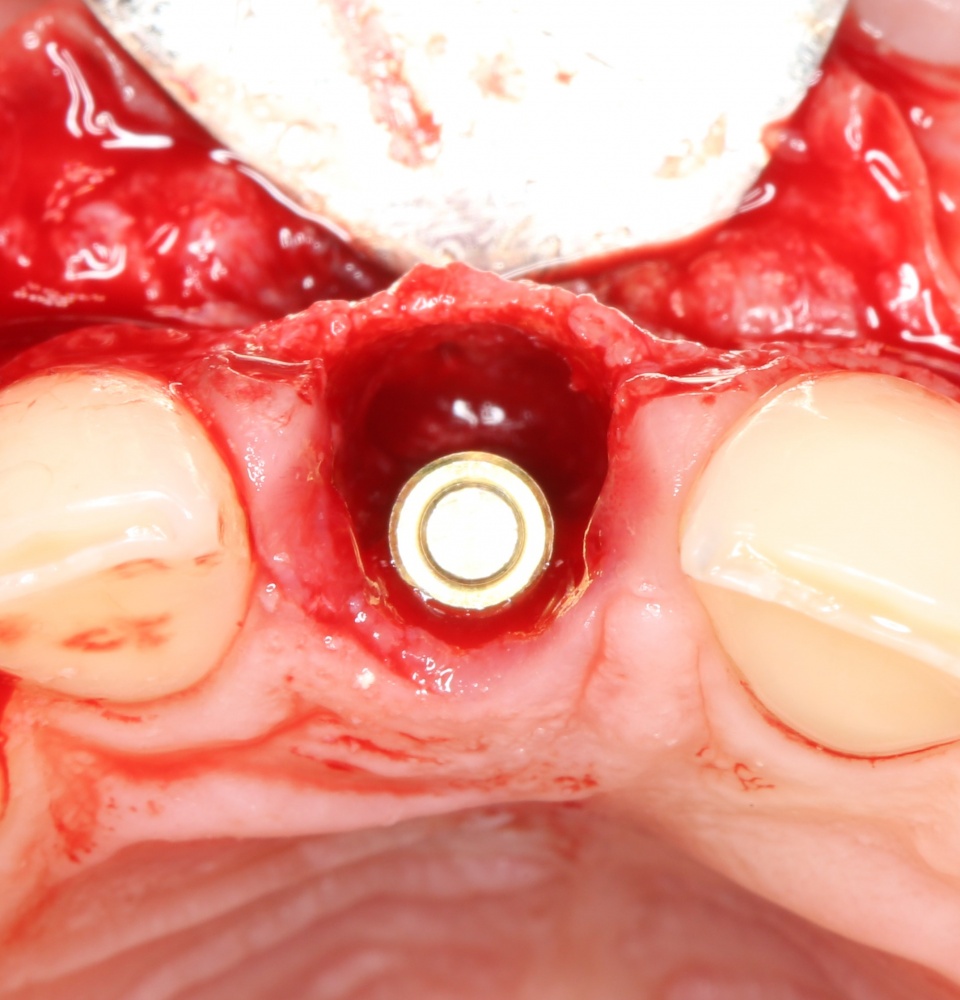

Вернемся к нашему клиническому случаю. Мы уже поставили импланты с расчетом на будущую высоту альвеолярного гребня и положение будущих зубов:

И, если в предыдущей части мы рассматривали ситуацию, когда принимающее ложе имеет относительно простой рельеф, и у нас не возникло сложностей с адаптацией аутоблока, то в случае, рассматриваемом сегодня, нормальная и точная адаптация крупного костного фрагмента, практически, невозможна. Именно поэтому мы решили использовать направленную костную регенерацию (НКР), поскольку с адаптацией тестообразного по консистенции графта проблем, обычно, никогда не бывает. Как, например, в этом случае:

В описываемом клиническом случае нам нужно замещать достаточно большой объем костной ткани, поэтому использование ксенографта (Geistlich Bio-Oss) выглядит совершенно разумным. Мы смешиваем его с аутокостной стружкой, источником клеток и факторов роста костной ткани, в пропорции, примерно 50/50, получая, при этом, около 3 куб см готового к использованию графта:

С помощью него мы «достраиваем» недостающую часть альвеолярного гребня, полностью перекрывая импланты. Напомню, что субкрестальные Ankylos Dentsply Implants вполне допускают такой подход.